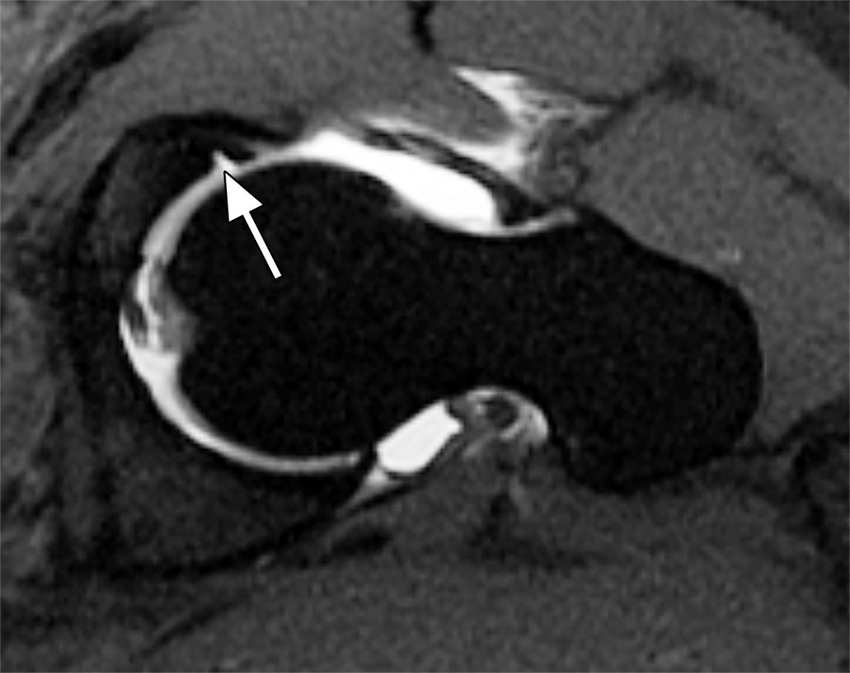

What does a hip labral tear look like on an MRI?

MRIs (magnetic resonance imaging) are imaging technology used to produce detailed images of the body’s soft tissue, in which dyes can also be injected to enhance those images (Cleveland Clinic, 2018; Mayo Clinic Staff, 2019). Although using dye may enhance images, not all come back accurate and hence, doctors will need to use their best clinical judgement (Washington University Physicians, 2017). On the other hand, accurate MRIs are able to show how severe the labral tears are, and thus used often (Cleveland Clinic, 2018).

Labral tears of the hip look as though a part of the labrum is missing or detached from the rest of it. Using an analogy, in an MRI, the labrum looks like a wrench that encapsulates the ball (the head of the femur). At the ends of the circular part of the wrench/labrum, from a sagittal view (viewing the body separated from the front and back), it typically looks like a triangle. With a tear in the labrum, typically this triangular section of the labrum is detached or sectioned off from the rest of the labrum.